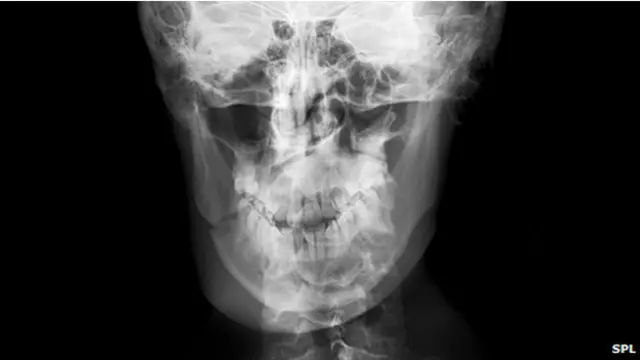

El informe médico pormenorizó que el paciente presenta un Traumatismo Encéfalo Craneano (TEC), lesiones oculares en ambas cuencas y la fractura total de los huesos faciales. Si bien el responsable del hecho ha sido plenamente identificado por las fuerzas del orden, actualmente continúa evadiendo a la Justicia.